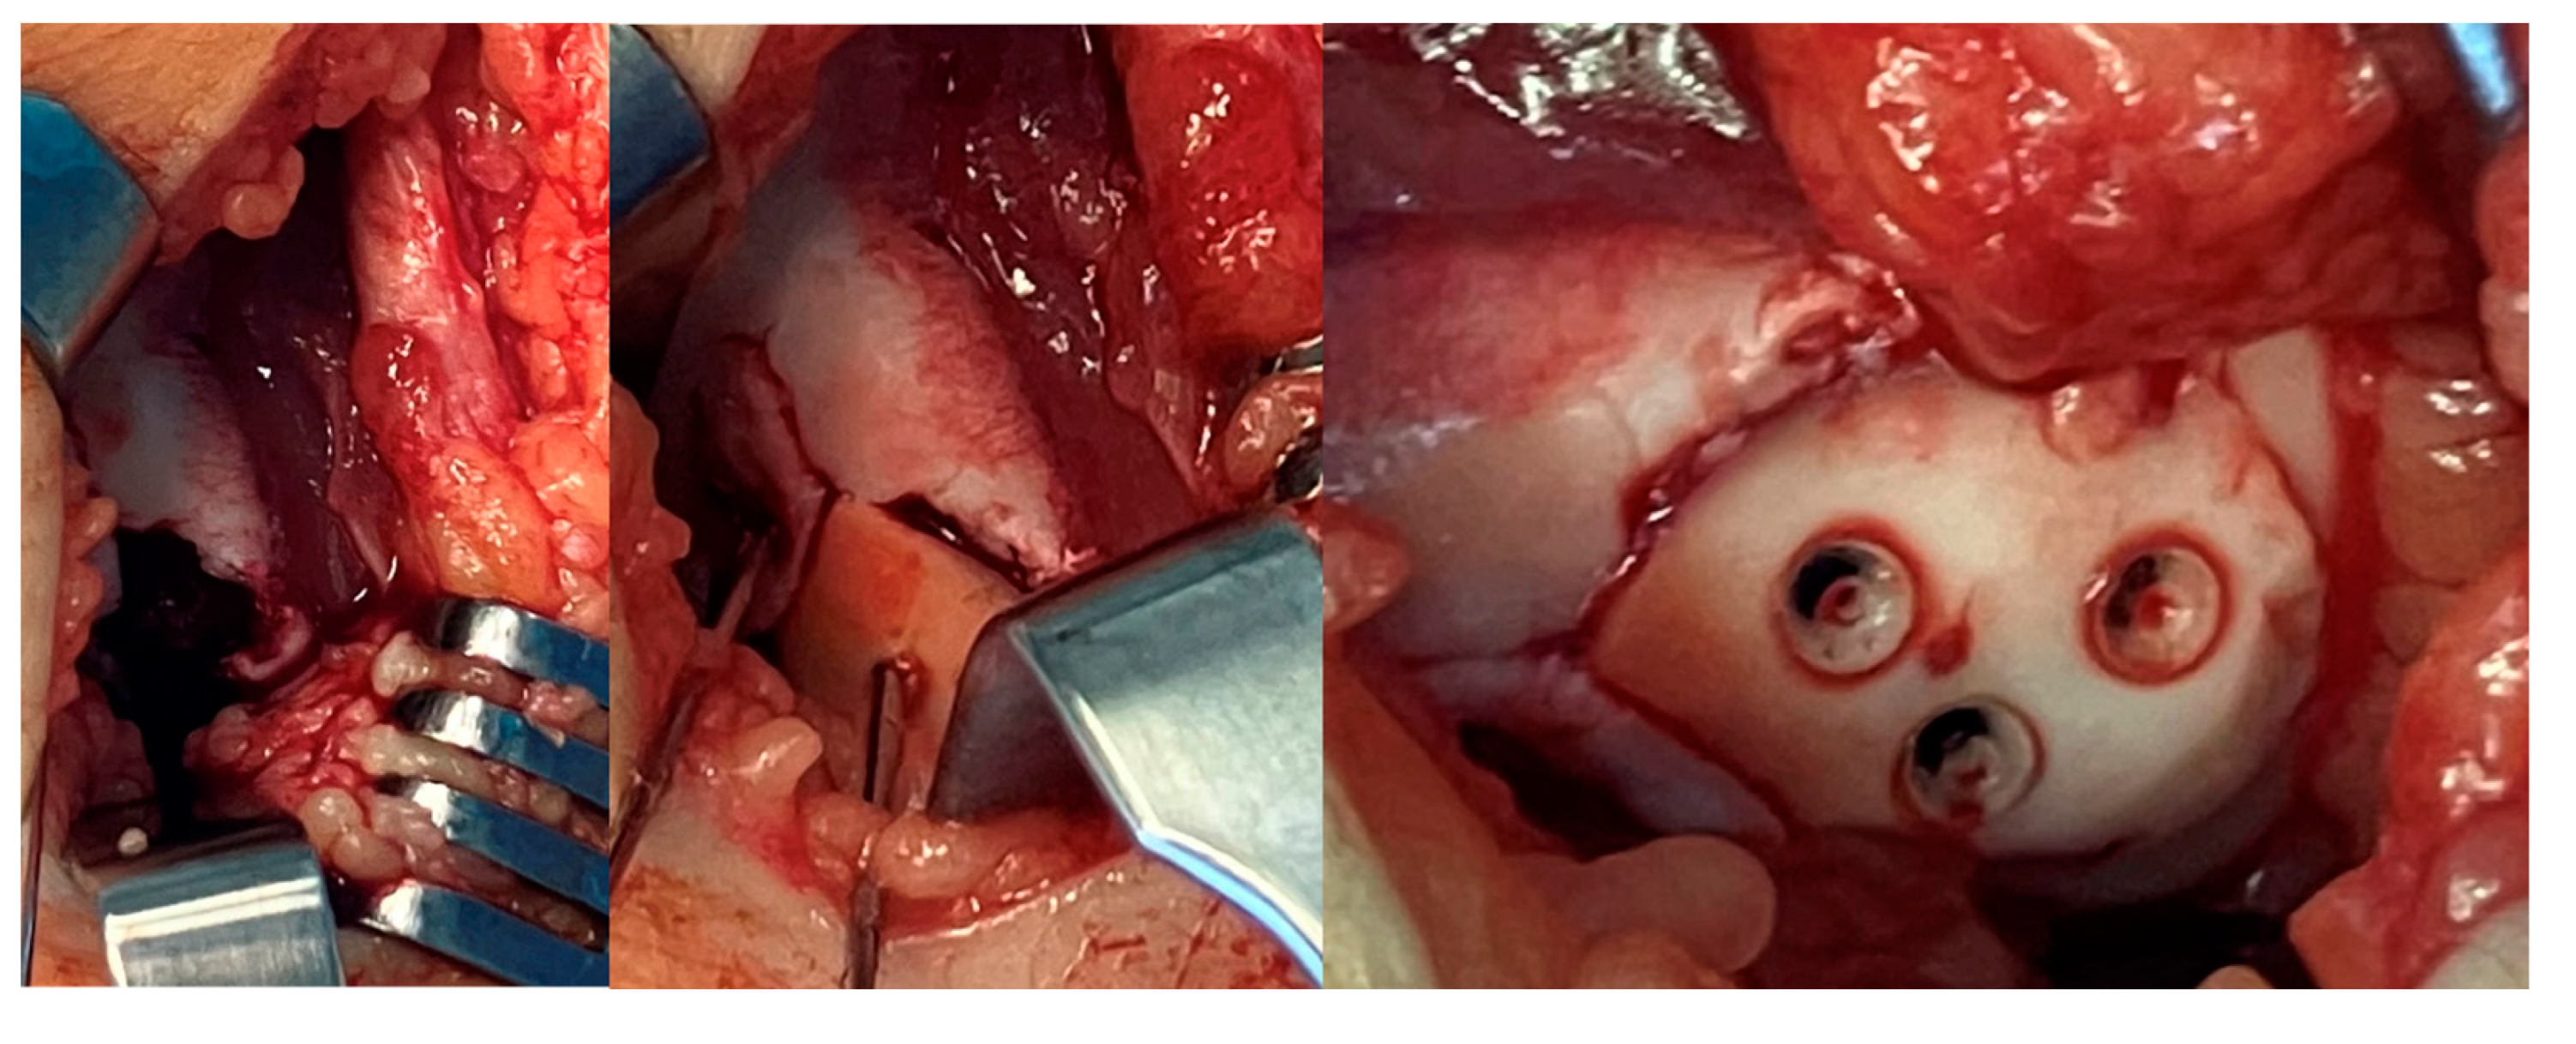

2.2. Surgical Methods: